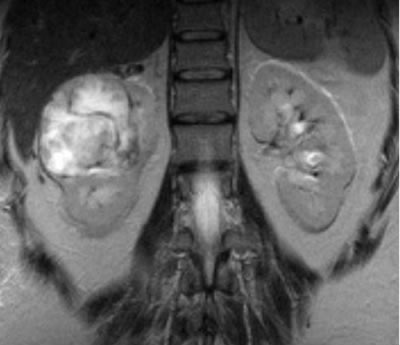

МРТ |

|

МРТ – регионарные лимфоузлы

увеличены до 15-17 мм в диаметре, в желчном пузыре

несколько камней с максимальным размером 6-7 мм